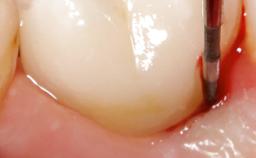

Open-Flap Debridement for the Management of Peri-Implant Mucositis Associated with Excess Cement

A 79-year-old female patient was referred to the Department of Periodontology of the University of Bern, Switzerland by her private dentist in May 2019. She had been rehabilitated in May 2005 with two tissue-level implants (Institut Straumann AG, Basel Switzerland) at sites 13 and 15, supporting a three-unit cemented fixed dental prosthesis (FDP). The metal-ceramic FDP had been cemented permanently with a glass-ionomer cement (Ketac Cem; 3M ESPE, Seefeld, Germany). Implant 13 had been diagnosed with peri-implant mucositis by the referring dentist in the course of regular supportive therapy. The patient was in good general health, did not smoke, and exhibited good self-performed plaque control.